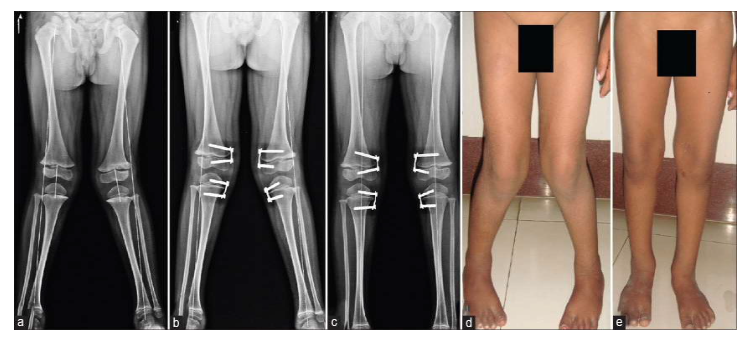

Ở tuổi vị thành niên với gối vẹo ngoài nặng gây lệch trục rõ rệt, có chỉ định điều chỉnh bằng phẫu thuật. Có hai phương pháp phẫu thuật: làm dính nửa bản sụn tăng trưởng (bên trong) đầu dưới xương đùi và/hoặc đầu trên xương chày và phẫu thuật cắt chỉnh xương (với xương trưởng thành).